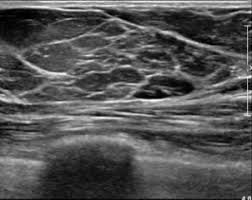

The ACUSON Maple Ultrasound System supports a full spectrum of breast and small-parts imaging applications, helping our specialists visualize fine tissue detail in real time without radiation exposure.

High-definition imaging: Exceptional spatial and contrast resolution to characterize tissue and detect small or complex lesions.

Targeted versatility: Designed for breast, thyroid, lymph node, and soft-tissue evaluations—essential in oncology diagnostics and treatment monitoring.

An interesting fact: ultrasound imaging (sonomammography) can reveal changes in soft tissue before they become visible on mammography, making it an invaluable tool for personalized, early-stage cancer care. Mammography is the gold standard for breast cancer screening, but ultrasound adds critical detail—especially in women with dense breast tissue, where small abnormalities may be hidden on X-ray images. Using both technologies together allows our physicians to: